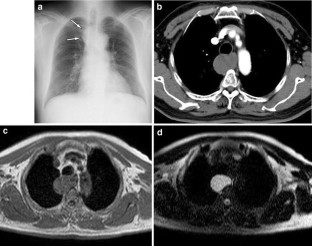

Fig. 3